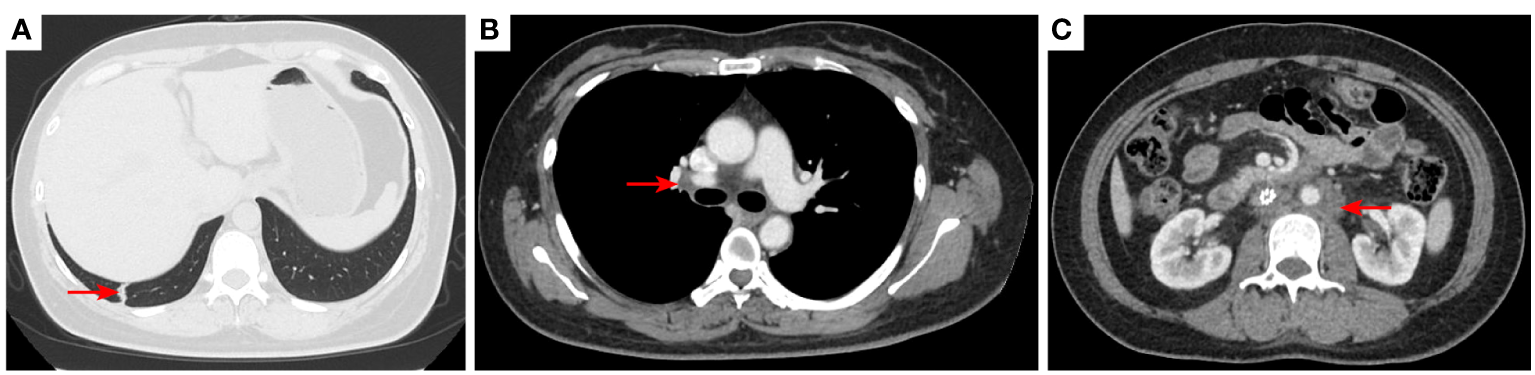

Figure 8

2021–8-24: Length of metastatic tumor in lower right lung 1.59 cm [red arrow, (A)]; short diameter of right hilar lymph node 1.53 cm [red arrow, (B)]; the short diameter of retroperitoneal lymph nodes was 1.61 cm, and the short diameter of left pelvic lymph nodes was 3.11 cm [red arrow, (C, D)]. The acetabulum was not scanned. The efficacy was SD. SD, stable disease.